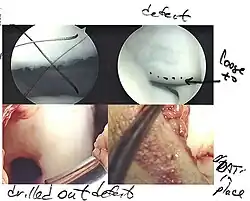

Arthroscopic image of OATS surgery on the medial femoral condyle of the knee

The choice of surgical versus non-surgical treatments for osteochondritis dissecans is controversial.[51] Consequently, the type and extent of surgery necessary varies based on patient age, severity of the lesion, and personal bias of the treating surgeon—entailing an exhaustive list of suggested treatments. A variety of surgical options exist for the treatment of persistently symptomatic, intact, partially detached, and completely detached OCD lesions. Post-surgery reparative cartilage is inferior to healthy hyaline cartilage in glycosaminoglycan concentration, histological, and immunohistochemical appearance.[52] As a result, surgery is often avoided if non-operative treatment is viable.